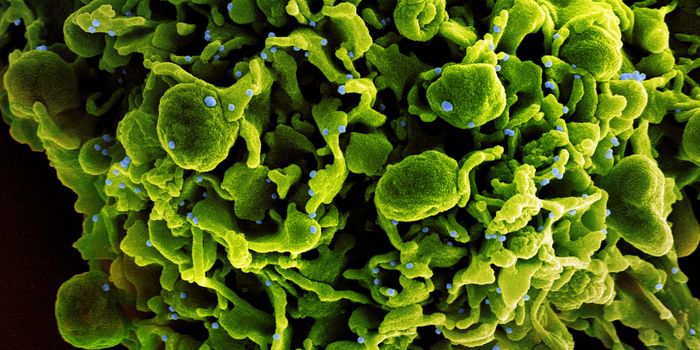

DEC 15, 2018Cell & Molecular BiologyResearchers have been trying to create a vaccine for HIV, the virus that causes AIDS, for decades.